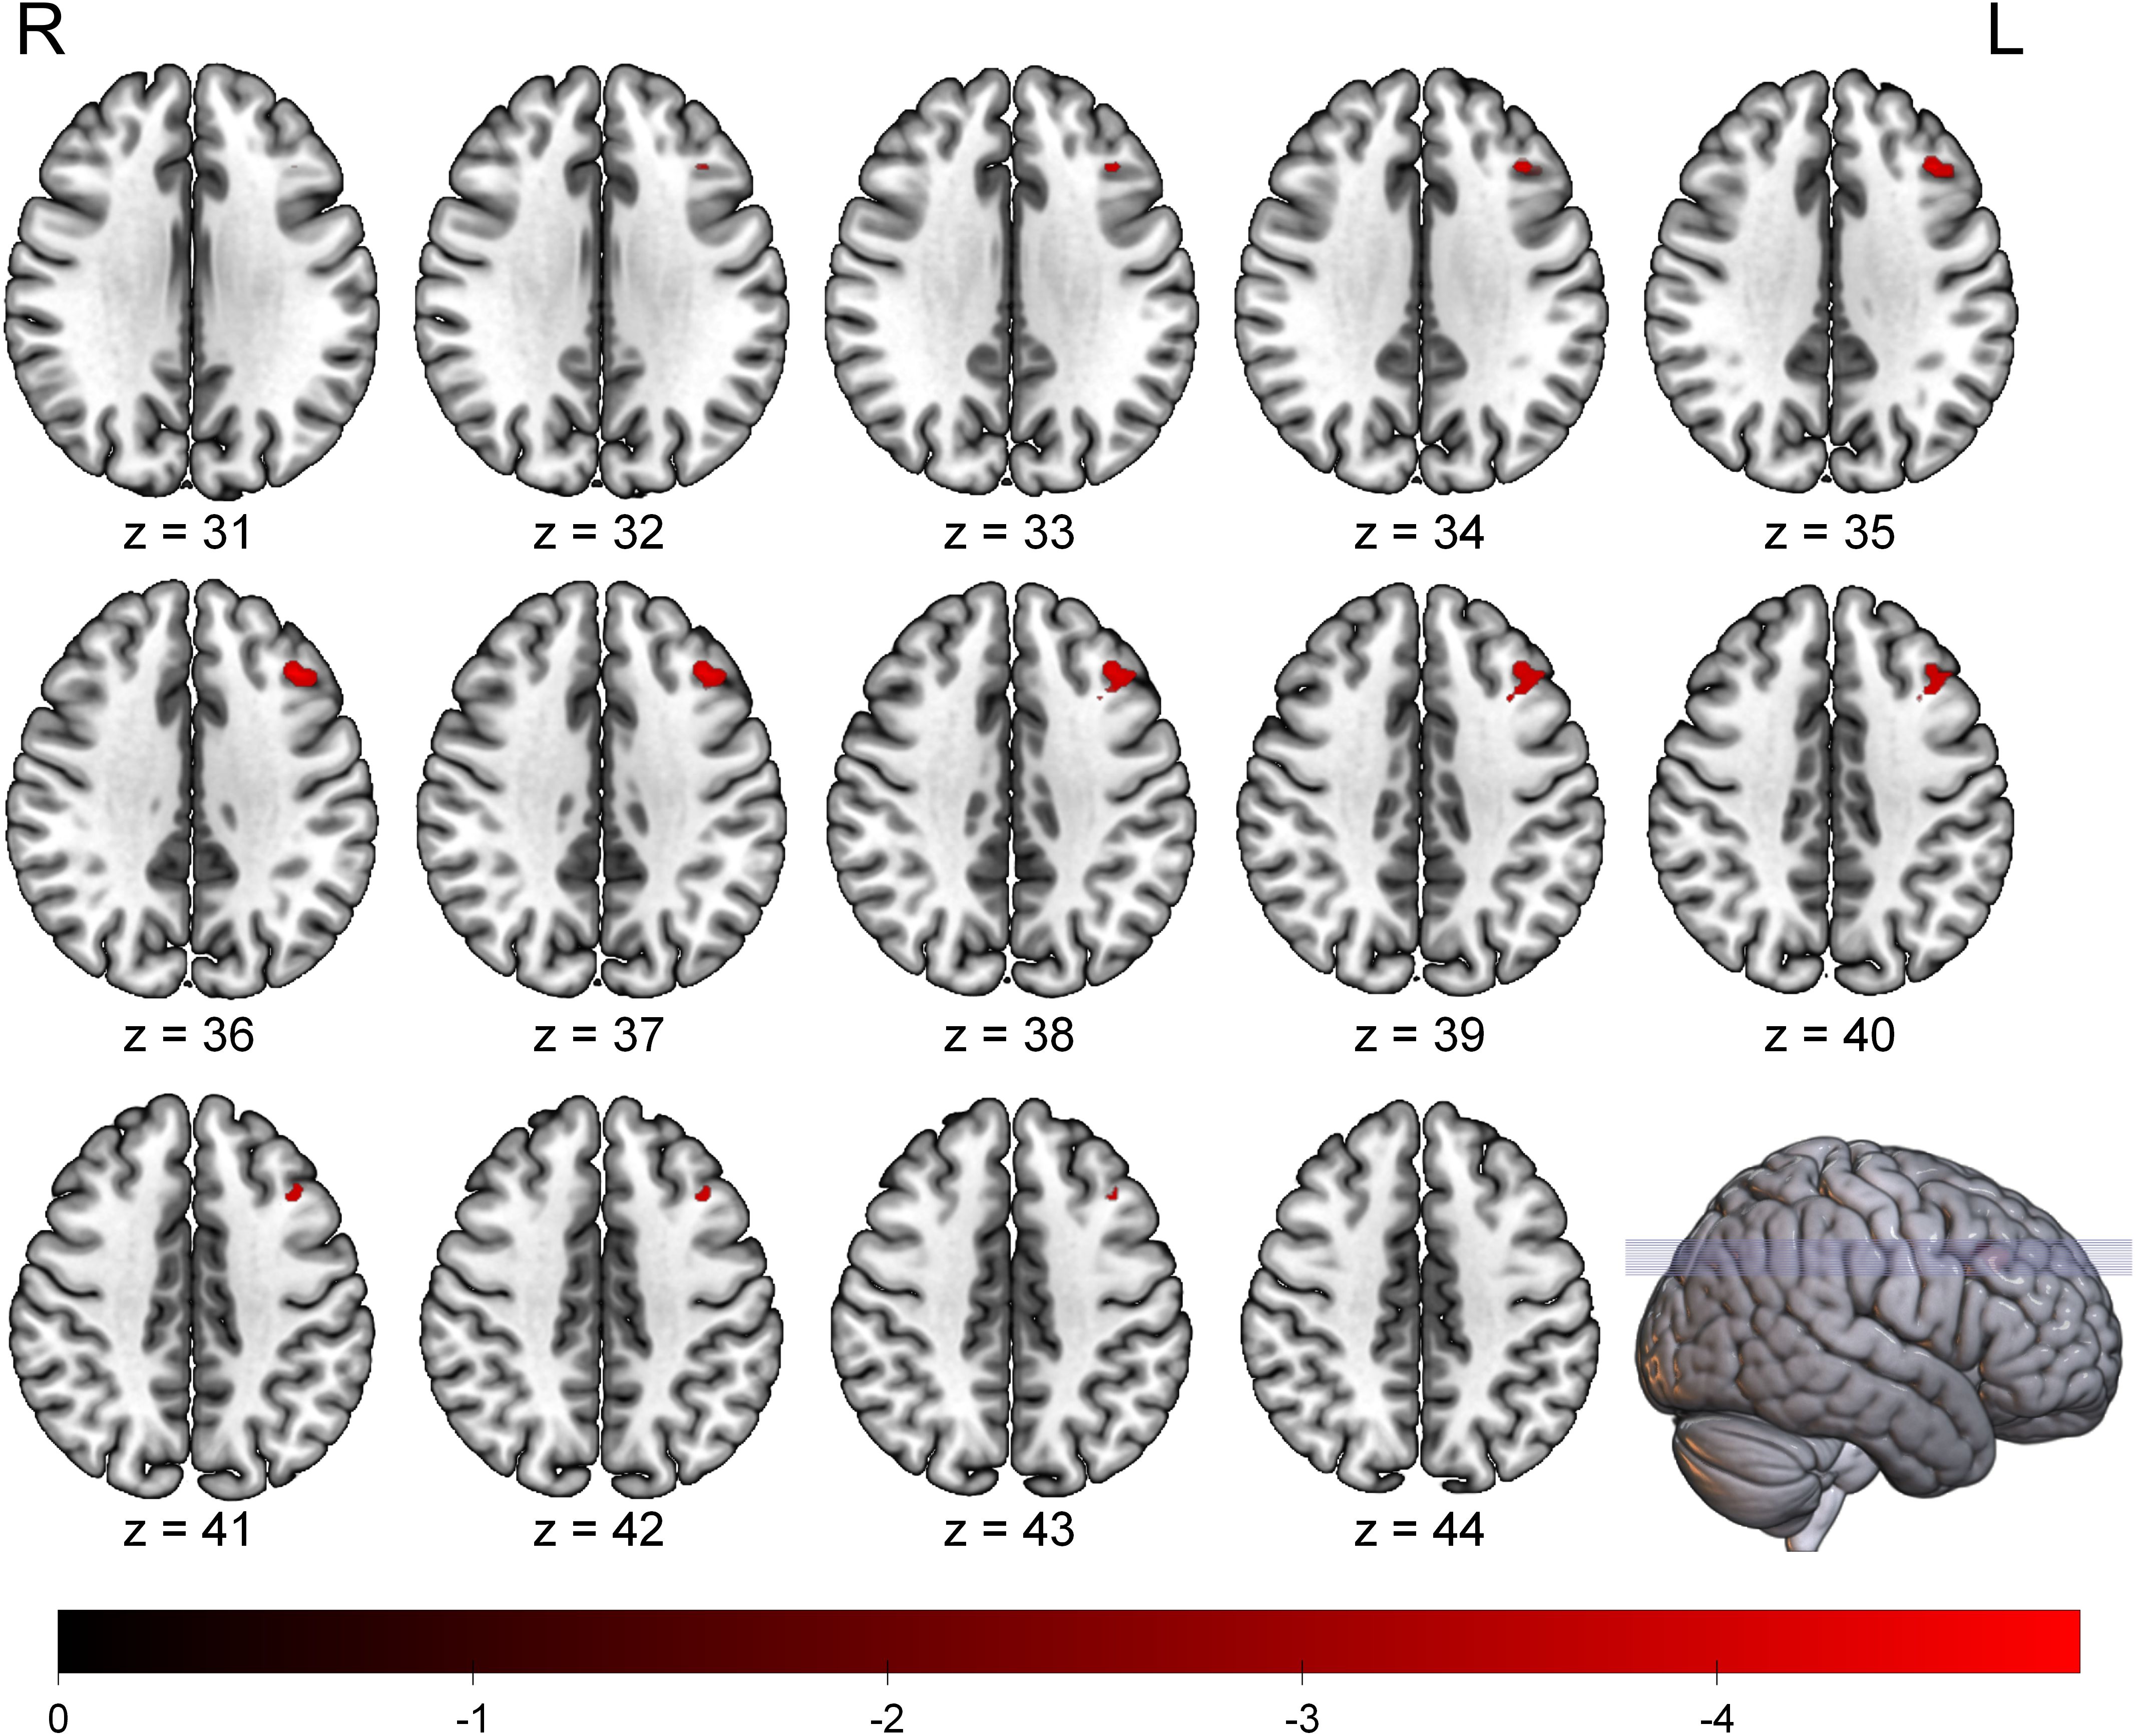

The whole-brain voxel-wise analysis revealed a significant negative correlation between ALFF values and BSI scores in a single brain cluster. This cluster was located in the left Middle Frontal Gyrus (MFG). The detailed statistical information for this cluster is presented in Table 2. The anatomical location of this cluster is visualized in Figure 1. To further investigate this relationship, the mean ALFF values were extracted from the left MFG cluster for post-hoc analysis. A Spearman correlation analysis confirmed a significant negative relationship between the ALFF values of the left MFG and the BSI scores (ρ = -0.42, p < 0.001), as illustrated in Figure 2. This indicates that lower spontaneous brain activity in the left MFG is associated with higher levels of suicidal ideation in adolescents with NSSI.

Figure 1

Sequential brain MRI scans display axial slices from z = 31 to z = 44, highlighting areas of activation in red. A color scale from 0 to -4 is provided below, with a 3D brain model to the right.

Figure 1. Brain region showing a significant negative correlation between ALFF values and BSI scores in adolescents with NSSI. The significant cluster in the left middle frontal gyrus is overlaid on a standard MNI template brain. The color bar indicates the T-values of the correlation. Statistical maps were set at a threshold of FDR correction (p < 0.05, cluster size > 20 voxels). ALFF, Amplitude of Low-Frequency Fluctuation; BSI, Beck Scale for Suicide Ideation; FDR, False Discovery Rate; L, Left; R, Right.